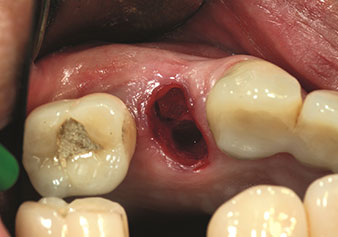

Gestion alvéolaire

Une application souvent sous-estimée est l’extraction atraumatique de racines dentaires ou de fragments radiculaires dans le cadre d’une gestion alvéolaire. Les périotomes à denture fine, qui sont actuellement disponibles en deux versions (EX1 et EX2 de W&H), peuvent également être utilisés pour extraire facilement des dents qui ont subi un traitement endodontique spécifique préalable ou des racines ankylosées. On obtient des alvéoles d’extraction dans lesquelles à la fois les tissus durs et les tissus mous sont entièrement préservés.

Ceci instaure des conditions optimales pour un traitement implantaire ultérieur ou immédiat (Figures 1 et 2 fournies avec l'autorisation du Dr Torsten Conrad, Bingen

am Rhein).